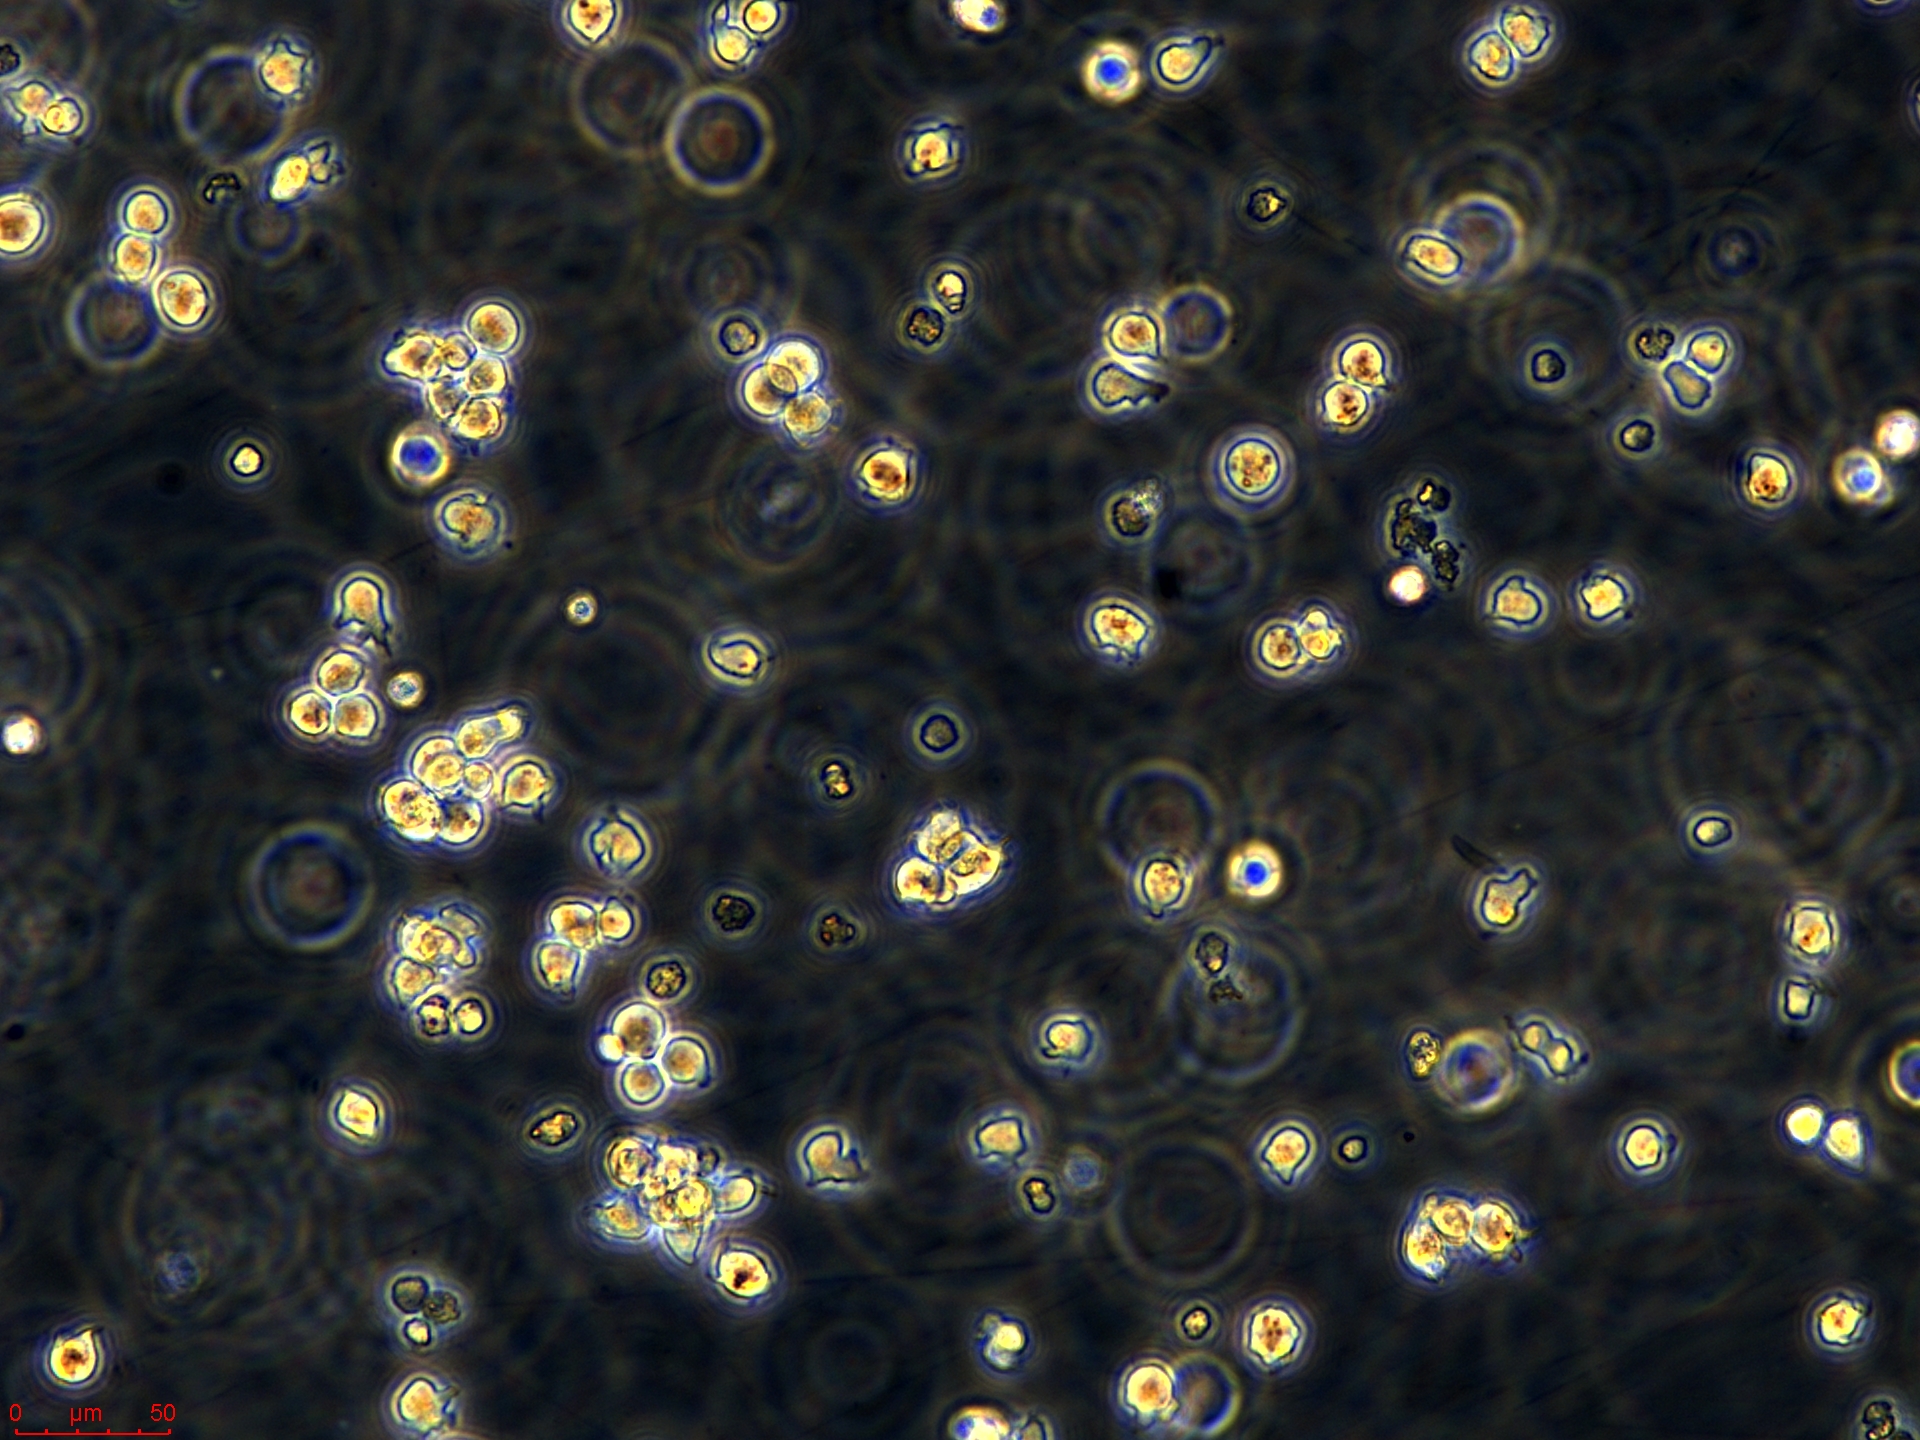

Jurkat细胞(人外周血白血病T细胞),是一种悬浮细胞。我的经验如下:1、培养液:RPMI1640,15%小牛血清,2%Na2CO3,1%HEPES,青霉素100IU/1ml,庆大霉素100IU/ml;2、培养条件:5%CO2,37度,30%湿度;3、细胞复苏:要快速将冻存管放入37度水中,不断轻轻摇晃,直到细胞完全溶解,加入10ml左右的培养液,800~1000rpm,10分钟离心,之后倒掉液体,加入新的培养基就可以进行培养了;4、细胞培养:起初进行传代时由于细胞刚刚复苏,长得比较